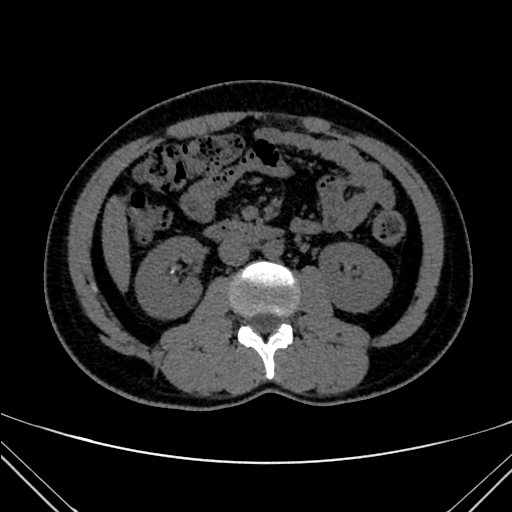

img

Tumor